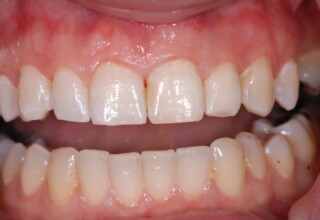

Αποκατάσταση διαστημάτων μεταξύ κεντρικών και πλαγίων τομέων

Τα διαστήματα έχουν δημιουργηθεί κυρίως λόγω των στενών πλαγίων. Μετά την ολοκλήρωση της ορθοδοντικής θεραπείας τα διαστήματα “έκλεισαν” με την τοποθέτηση δύο αποκαταστάσεων σύνθετης ρητίνης.